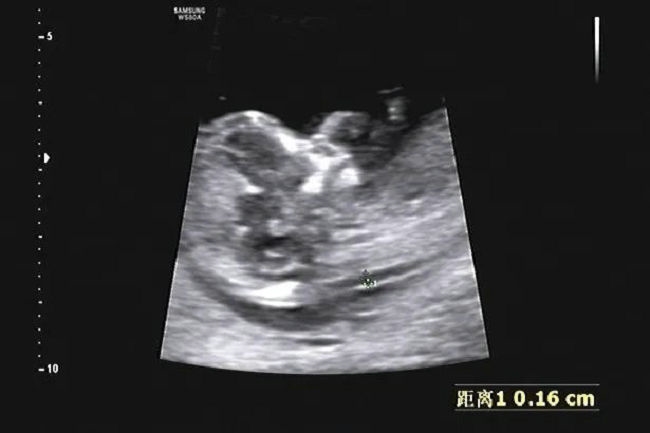

NT检查主要是在孕11周-孕14周之间(胎儿头臀长45mm-84mm之间)进行,通过彩超检查测量胎儿颈部透明层厚度,从而了解其是否存在染色体异常,或者唐氏综合征的风险。

NT测值<2.5mm都属于正常,>2.5mm提示异常风险增加,如果测量值>6.5mm,有80%不良妊娠结局风险。NT是筛查类检查,准确率约为70%。数据异常提示宝宝罹患唐氏综合征风险增高,结合早期唐筛的指标(血清中妊娠相关血浆蛋白-A(PAPP-A)、绒毛膜促性腺激素(HCG))和孕妇其他临床信息,来判断胎儿患唐氏综合征、神经管缺陷的危险系数。